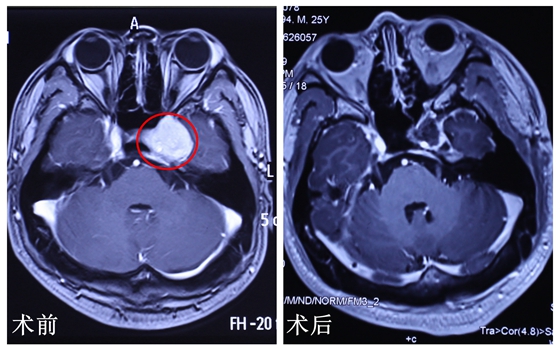

今年25岁的小马两年前头痛发作,第一次发作持续了7天,第二次发作持续了2天,第三次发作持续了5天,而且疼痛一次比一次剧烈,“就像刀割似的”小马来到湘雅常德医院后如此描述道。起初全家人都觉得是感冒、鼻炎惹的祸,可是小马的话让他们警觉了,去到当地医院检查发现,病变处在脑袋的正中心,是既往手术禁区海绵窦神经鞘瘤。

海绵窦(cavemoussinus)是位于蝶鞍两侧硬脑膜两层间不规则的腔隙,左右各一。海绵窦是接收来自眼上、下静脉和颞前静脉的静脉回流,随后静脉血引流至岩上、下静脉窦和斜坡基底静脉丛,海绵窦内膜又包绕了第Ⅲ,第Ⅳ,第Ⅵ神经,其位置深在,内含毗邻重要的血管神经,曾被视为手术禁区。又据核磁共振检查,此处的肿瘤将近3公分,如果要完整切除此处的肿瘤,又不伤及重要的血管和神经,可以说难度极大。